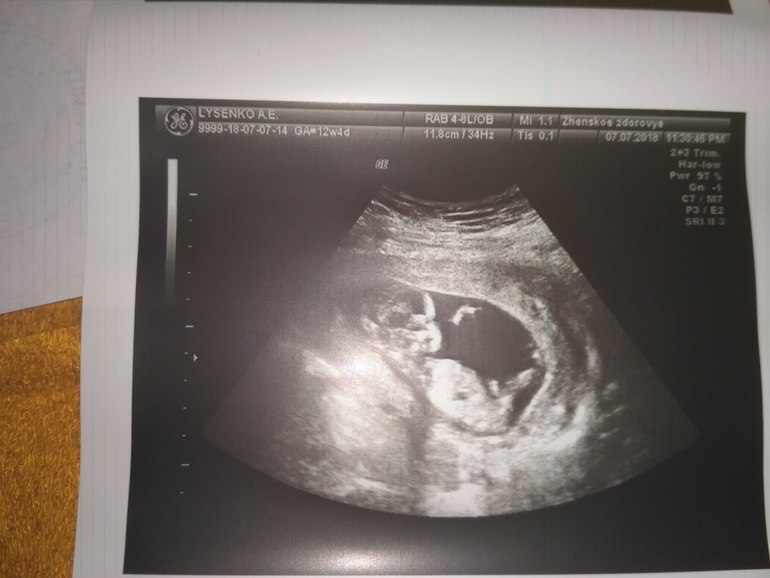

Ребёнок 😋причинное место закрыто ножкой, а если по форме черепа, то больше девочка, чем мальчик, мне кажется.

Я бы предположила девочку ;) Я заметила, у них более округлая нижняя челюсть (подбородок). У мальчиков угловатая.